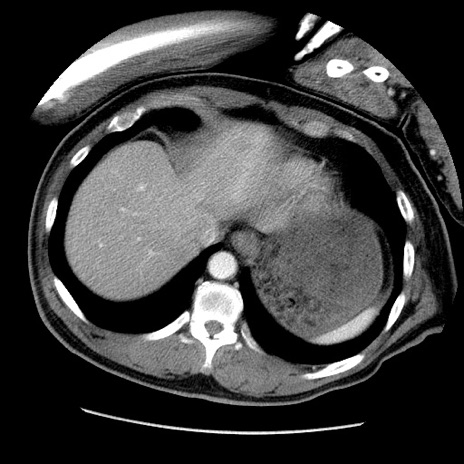

冠状断像

症例22(横断像)

【症例】50歳代男性

【主訴】腹痛

【現病歴】AVMからの被殻出血のため回復期リハ病棟入院中。 本日午後3時頃急に下腹部痛が出現した。

【既往歴】AVM、被殻出血、虫垂炎、高血圧

【身体所見】意識晴明、左半身不全麻痺、会話の理解は良好、36.5°C、腹部:膨隆、全体に板状硬、下腹部正中に圧痛点あり、反跳痛-、筋性防御不明、右下腹部にope scar

【データ】WBC 9400、CRP 0.06